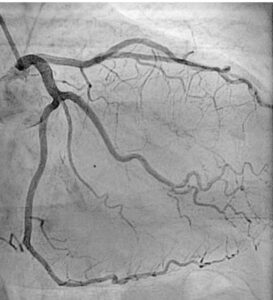

Coronary Angiography Test in Pimpri Chinchwad

Our Coronary Angiography Test helps detect blockages and assess the health of your heart’s arteries. At our Pimpri Chinchwad clinic, expert cardiologists perform this safe and accurate test using advanced imaging technology. Early diagnosis through this test allows effective treatment for heart conditions. Book your coronary angiography test today for better heart care.